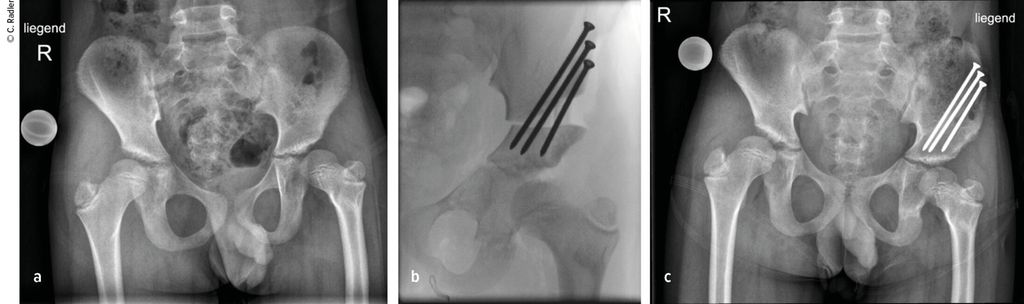

Pathologie am Kniegelenk

Die Valgusstellung kann sehr einfach über eine Wachstumslenkung (Hemiepiphysiodese mit 2-Loch-Platte) korrigiert werden. Um eine Subluxation am Kniegelenk zu verhindern, muss bei allen diesen Fällen bei Verlängerung mit Fixateur dieser knieüberbrückend montiert werden (Abb.4). Bei Verlängerung über einen Verlängerungsmarknagel wird in diesen Fällen eine Oberunterschenkelschiene (KAFO) verwendet und prophylaktisch, soweit noch vorhanden, die Fascia lata auf Höhe des oberen Patellapols durchtrennt. Bei deutlicher Instabilität oder auch Subluxation ist eine Stabilisierung über eine komplexe Operation, die als Super-Knee-Operation subsumiert wird, erforderlich.2 Diese Operation kann auch an die Hüftrekonstruktion/Super-Hip-Operation angeschlossen werden, da hier die Faszie ohnehin präpariert wird. Je nach Alter des Patienten und dem Ausmaß der Instabilität wird hierbei die Fascia lata nach Präparation bis an das Tuberculum Gerdyi und Halbieren der Länge nach entweder extraartikulär oder intraartikulär geführt. Auch die Fixation wird abhängig vom Alter mit Biotenodeseschrauben oder Weichteilzügelung durchgeführt.

Abb. 4: Platzierung (a–d) eines Fixateur externe mit Knie-Überbau (e–g) zum Schutz vor (Sub-)Luxation